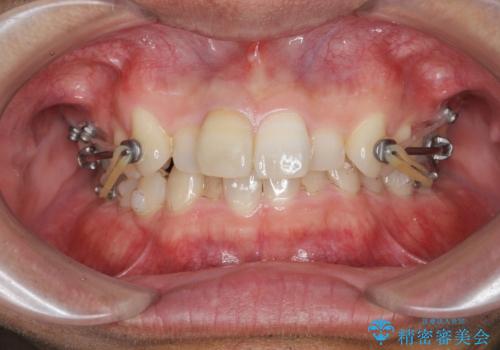

・深い噛み合わせ(ディープバイト) ・2級性の咬合関係(上顎前突)・前歯のがたつき

以上のような歯並びの問題をマウスピース矯正インビザライン・カリエール・マイクロインプラント・部分ワイヤー矯正

を用いて改善していきます。